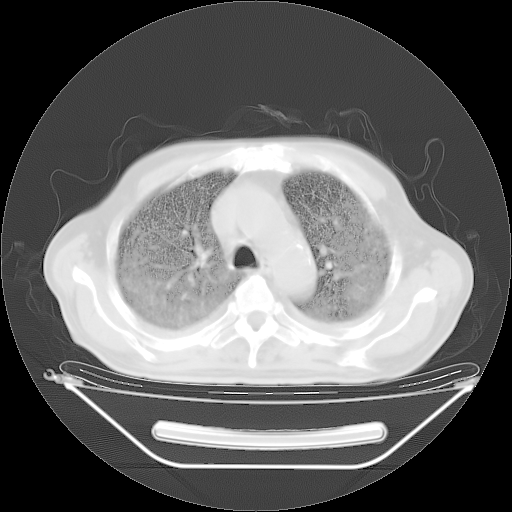

今天复查肺部CT,发现双肺广泛磨玻璃样改变。所以我把3月19日和5月9日相隔50天的肺部CT上传。请大家会诊。

2009年3月19日肺部CT片。

2009年3月19日肺部CT